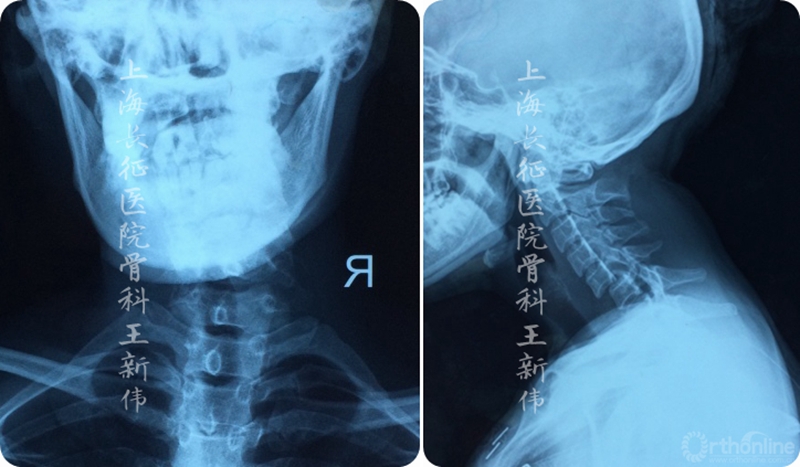

第一次术前颈椎X线正侧位片

第一次术后颈椎X线片